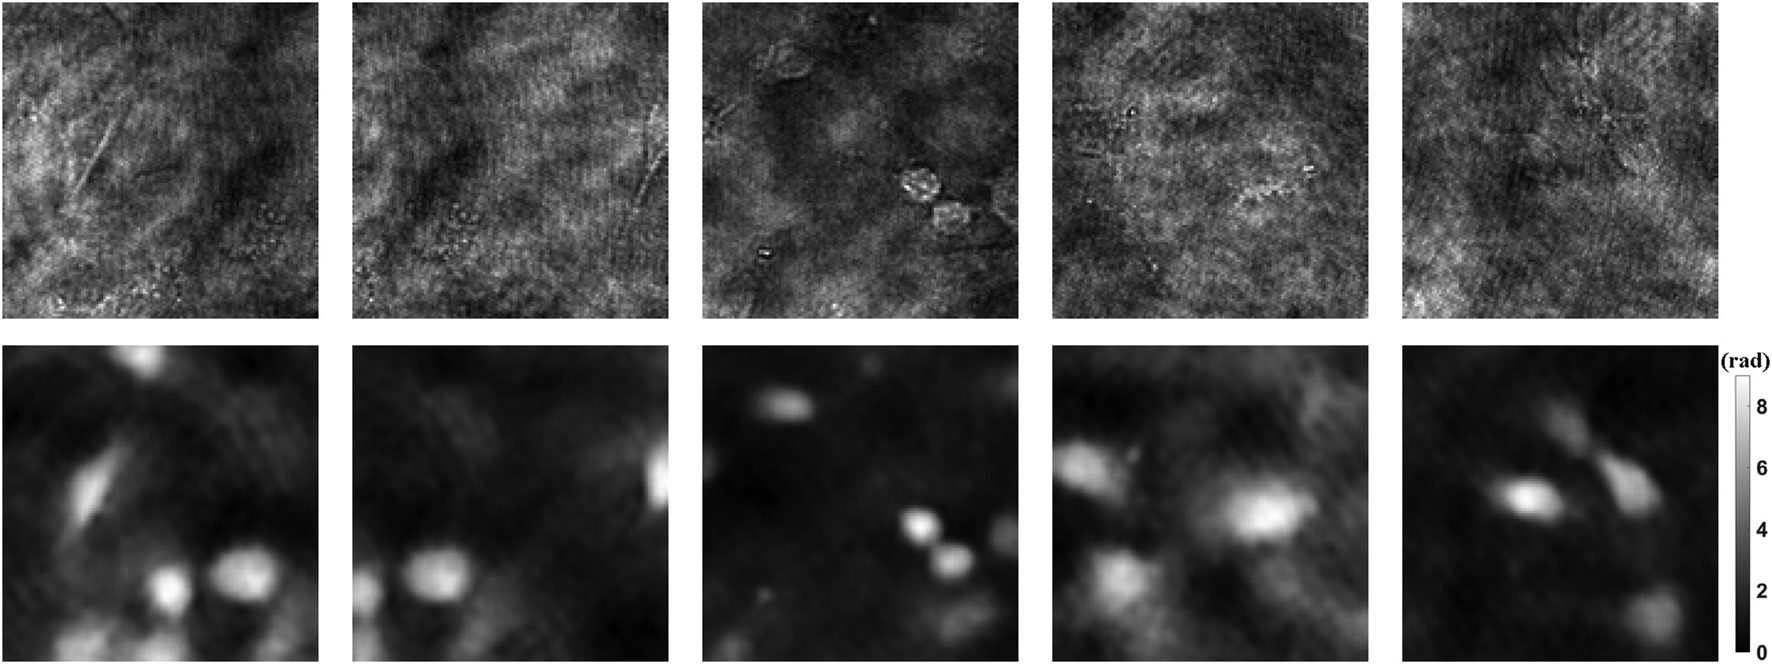

1990 holograms of mouse osteoblastic cells are taken with DLHM. Then the phase images are recovered by traditional convolution algorithm. In order to improve the generalization ability of the neural network, data augmentation is a standard method. The dataset including 1990 holograms and corresponding phase images is expanded to 10,000 by flipping, rotating, etc. After that, the holograms and phase images of each cell are used as input and ground truth, respectively. Figure 3 shows part of the dataset. Among all the data, 90% are used for training, 10% for testing. Then we can use the prepared dataset to train the neural network PhaseNet.

FIGURE 3

Dataset examples. The upper part shows the holograms as input, and the lower part shows the phase results as ground truth.

After training, we feed the holograms in the test set to PhaseNet, and the corresponding phase results are quickly reconstructed. Part of the results is visualized in Figure 4. Figures 4A,B are the ground truth and corresponding reconstruction results, respectively. From the two-dimensional phase images of the cell, we can see that the results of the network reconstruction are very close to the ground truth. More quantitatively, we calculated its structural similarity index measure (SSIM), which is used for measuring the similarity between two images and is a perception-based model that considers image degradation as perceived change in structural information, while also incorporating important perceptual phenomena, including both luminance masking and contrast masking terms. Finally, the SSIM of the phase results obtained using PhaseNet can reach 0. 9404. This shows that PhaseNet can replace traditional algorithms to achieve the numerical reconstruction of holograms. Figure 4C shows the three-dimensional phase images of the cells obtained by PhaseNet.